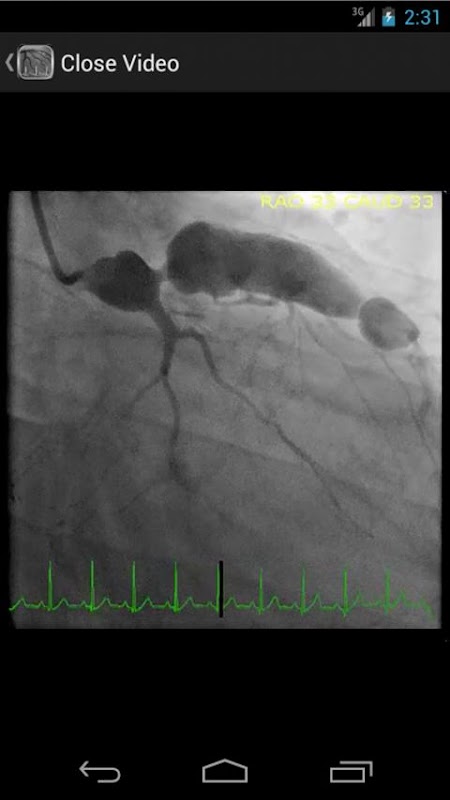

* Searchable database containing more than 30 videos (coronary angiograms, ventriculograms, and aortograms) of both common and rare findings in the cardiac catheterization lab